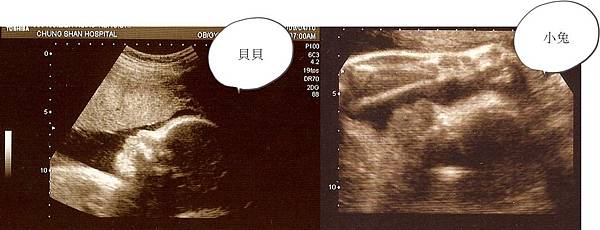

這是上周小兔的照片。健保給付的超音波其實很少,距離上回高層次超音波見到小兔已經過了快3個月了,好期待喔!

從側面看起來,兩兄弟長的幾乎一模一樣!可以看出小兔似乎也是個扣桃寶寶喔(爸比的遺傳因子一定要這麼強嗎?)

不過正面就不一樣了~~貝貝跟媽咪一樣有著瘦長的臉型,小兔則似乎遺傳到把拔,有著圓圓的澎澎臉 呵呵~讓我也好想看看小兔到底長得啥模樣喔!